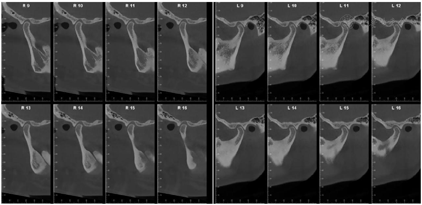

X线示37区于就诊前外院植入种植体(位置较差),15、16种植体联冠,全口牙牙槽骨吸收至根尖1/2~根尖1/3,尤以11、22、32牙槽骨吸收为甚。双侧颞下颌关节区骨皮质连续,形态不完全对称。安氏Ⅱ类+骨性Ⅱ类;低角水平生长型;牙周炎(重度);牙列拥挤合并牙列散隙及三角间隙;深覆盖Ⅲ°;

经过矫正前的牙周系统治疗以及22个月的矫正加稳定并联合矫治期间定期的牙周维护治疗,矫治结束后患者上下牙列牙齿排列整齐,建立了正常的覆牙合覆盖,维持了双侧磨牙、尖牙咬合关系,未有咬合干扰点,达到稳定的咬合关系。同时,牙周袋并未加深,11瘘管愈合(图2),全口牙龈颜色正常,牙周组织无活动性炎症出现,另外,患者口内治疗前多颗松动的牙齿,其松动度也有明显的改善,例如治疗前11、22松动Ⅲ°,23松动Ⅱ°,12、36~41松动Ⅰ°。治疗后11、22松动Ⅰ°,其余牙齿稳定无松动现象。X线表现(图9)治疗后牙槽骨吸收停止且23~26近远中,36远中以及27近中等部位均有少量牙槽骨再生,骨白线连续性亦有增加,下前牙区牙槽骨高度有少量增加。关节矢状面、冠状面保持稳定,FloridaProbe牙周检查最终探诊深度普遍降至1~3 mm。X线头影测量前后对比以及重叠图可见上前牙内收较明显,下切牙压低有效,侧貌突度明显改善(图10,图11,图12,图13,图14)。

1.研究表明牙周炎患者经牙周治疗2~6个月后,若达到菌斑控制良好、软硬组织无炎症且软硬组织厚度充足等条件,且经评估无正畸禁忌症时可行正畸治疗[6]。本病例经过规范的牙周基础治疗,并进行了下前牙的翻瓣手术,最终探诊深度普遍小于3 mm。从X片可见,牙槽骨吸收停止且23~26近远中、36远中以及27近中等部位均有少量牙槽骨再生,骨白线连续性亦有增加,下前牙区牙槽骨高度有少量增加,达到正畸治疗的准入标准。